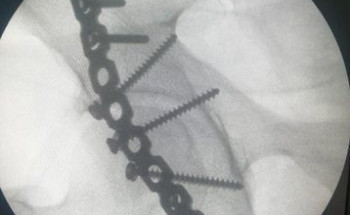

تدخل طبي ناجح في مستشفى القويعية مع حالة مصاب في حادث مروري

تعامل بنجاح فريق طبي في مستشفى القويعية العام مع حالة مصاب في حادث مروري تسبب له في كسور متعددة معقدة "كسور في الساق اليمنى، والحوض الأيمن "الجوف الحقي الأيمن".حيث تم اجراء عمل عملية لتثبيت الكسور، ...